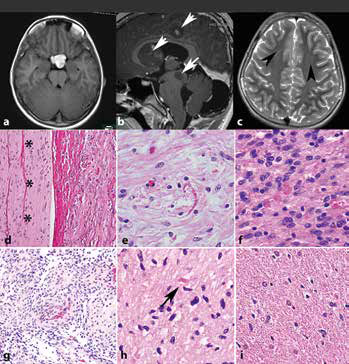

389-390期《全球肿瘤快讯》-107-.jpg

389-390期《全球肿瘤快讯》-106.jpg